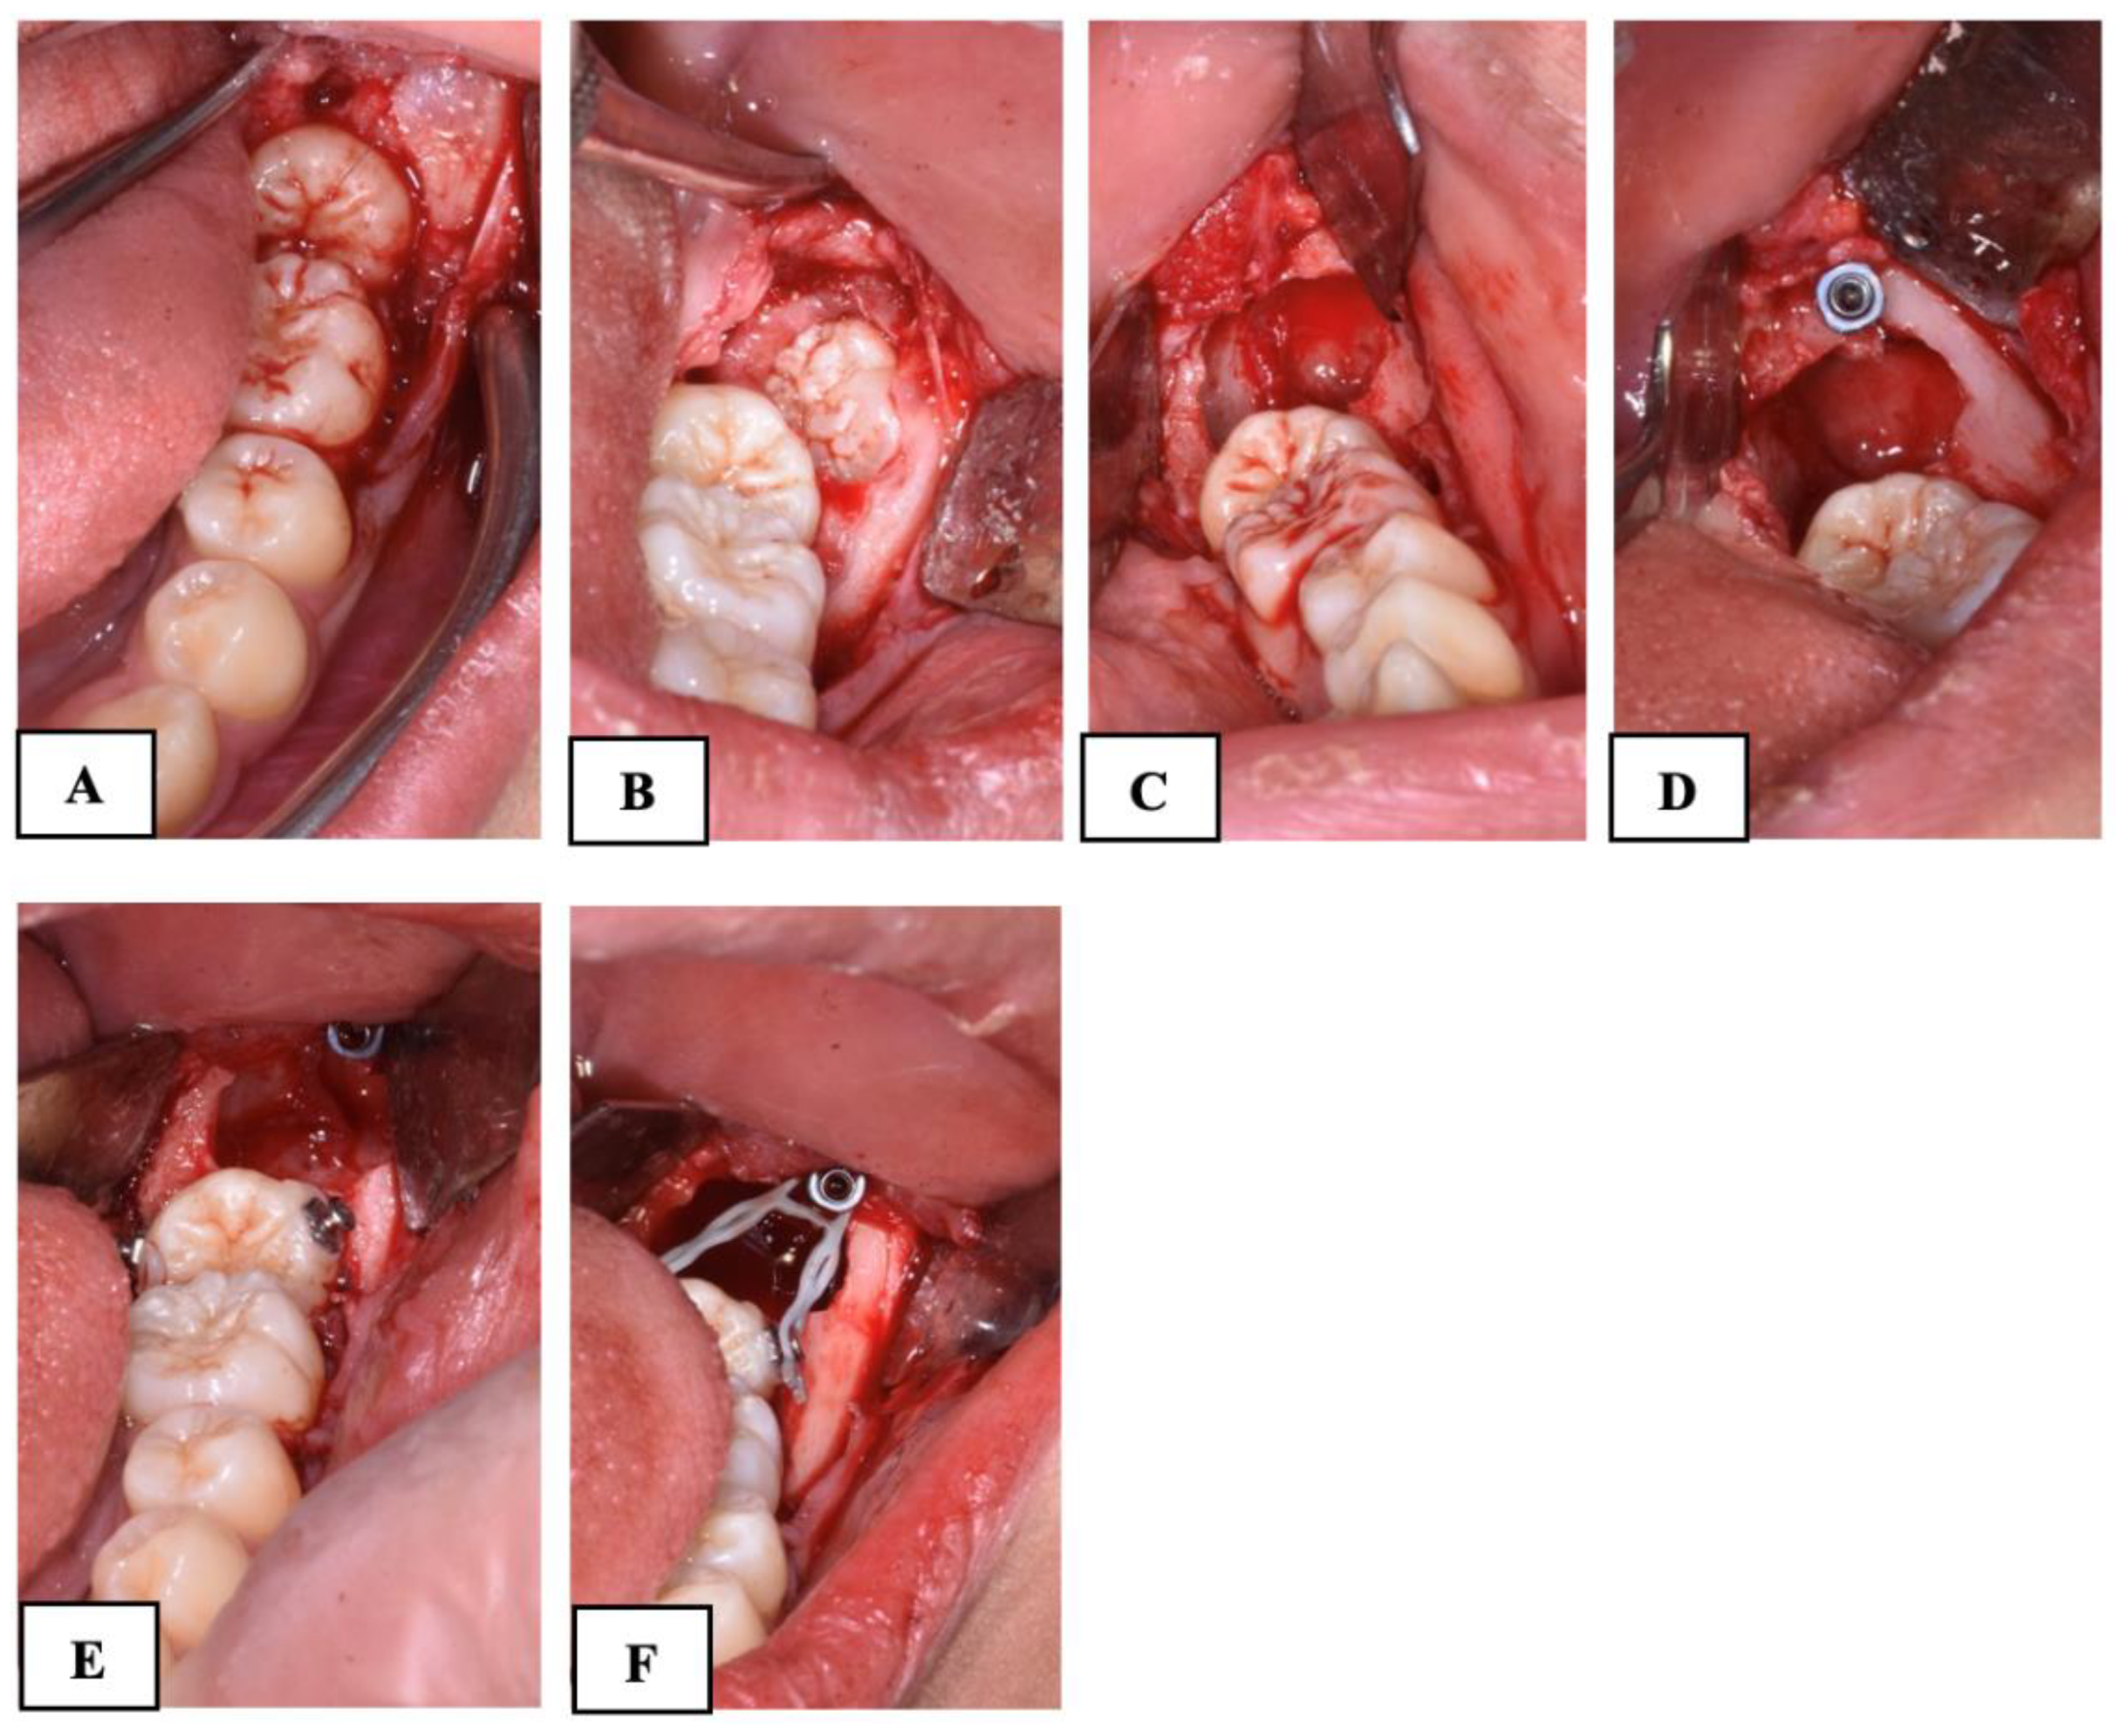

The angulation of the lower permanent second molar was measured on the panoramic radiograph as described by Evans [4]. Two lines were drawn connecting the tips of the cusps of the first and second molars; from these, two perpendicular lines representing the long axes of the teeth were traced. The angle formed between the long axes of the first and second molars was measured, representing the impaction angle of the second molar.

The impacted depth was measured, as described by Fu et al. [17], as the vertical distance from the distal marginal ridge of the first molar to the mesial marginal ridge of the impacted MM2 (Figure 1).

Figure 1. Orthopanoramic evaluation of angle (A) and depth (B) of impacted MM2.